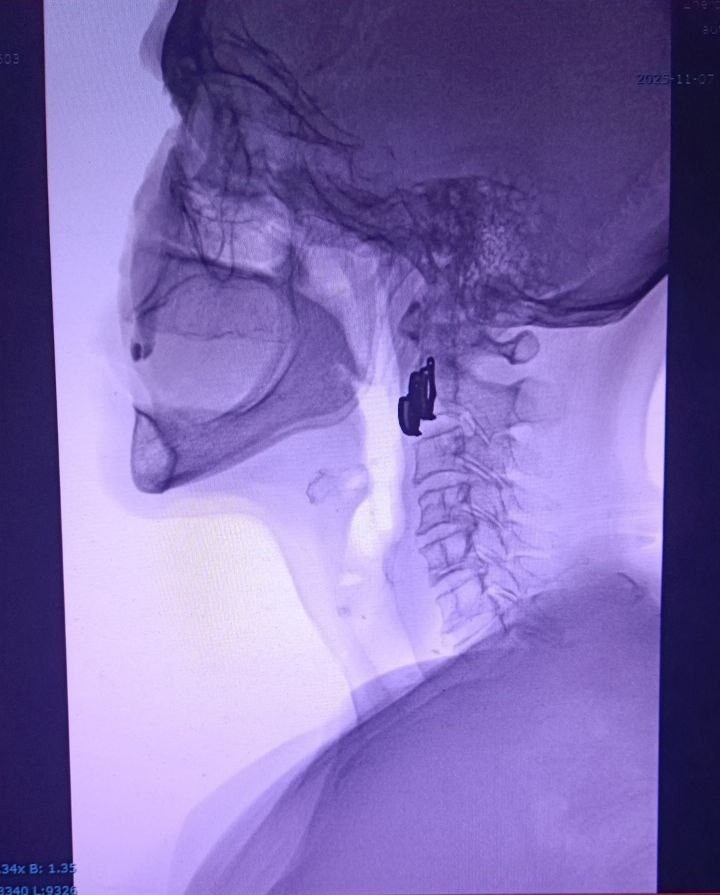

⚡️ Коллеги, предлагаем вам диагностический челлендж! Перед вами — рентгеновский снимок пациента с подозрением на инородное тело в ЖКТ. Ситуация: Пациентка 65 лет, обратилась на приемное отделение в 23:11 с жалобами на инородное тело в области шеи и боль при глотании. Из анамнеза — более суток назад употребляла рыбу семейства осетровых, подавилась. При осмотре ЛОР-врачом инородного тела рото-гортаноглотки не выявлено. Выполнен Рг снимок в боковой проекции, направлена для проведения эзофагоскопии. Рентгенолога в вечернее и ночное время в клинике нет. Перед проведением эзофагоскопии оцените боковой снимок, есть ли на нём изменения, характерные для инородного тела? Что нужно сделать: первому описать рентгенограмму по всем правилам, как это положено делать в клинической практике. ✔️ Для участия в конкурсе подпишитесь на наш Телеграм-канал и до 28 ноября включительно опубликуйте в комментарии к этому посту ваше описание снимка. 🏆 Приз победителю — деловой завтрак с Никитой Александровичем Щ

Пациентка 65 лет, обратилась на приемное отделение в 23:11 с жалобами на инородное тело в области шеи и боль при глотании. Из анамнеза — более суток назад употребляла рыбу семейства осетровых, подавилась.

При осмотре ЛОР-врачом инородного тела рото-гортаноглотки не выявлено. Выполнен Рг снимок в боковой проекции, направлена для проведения эзофагоскопии. Рентгенолога в вечернее и ночное время в клинике нет. Перед проведением эзофагоскопии оцените боковой снимок, есть ли на нём изменения, характерные для инородного тела?

Что нужно сделать: первому описать рентгенограмму по всем правилам, как это положено делать в клинической практике.